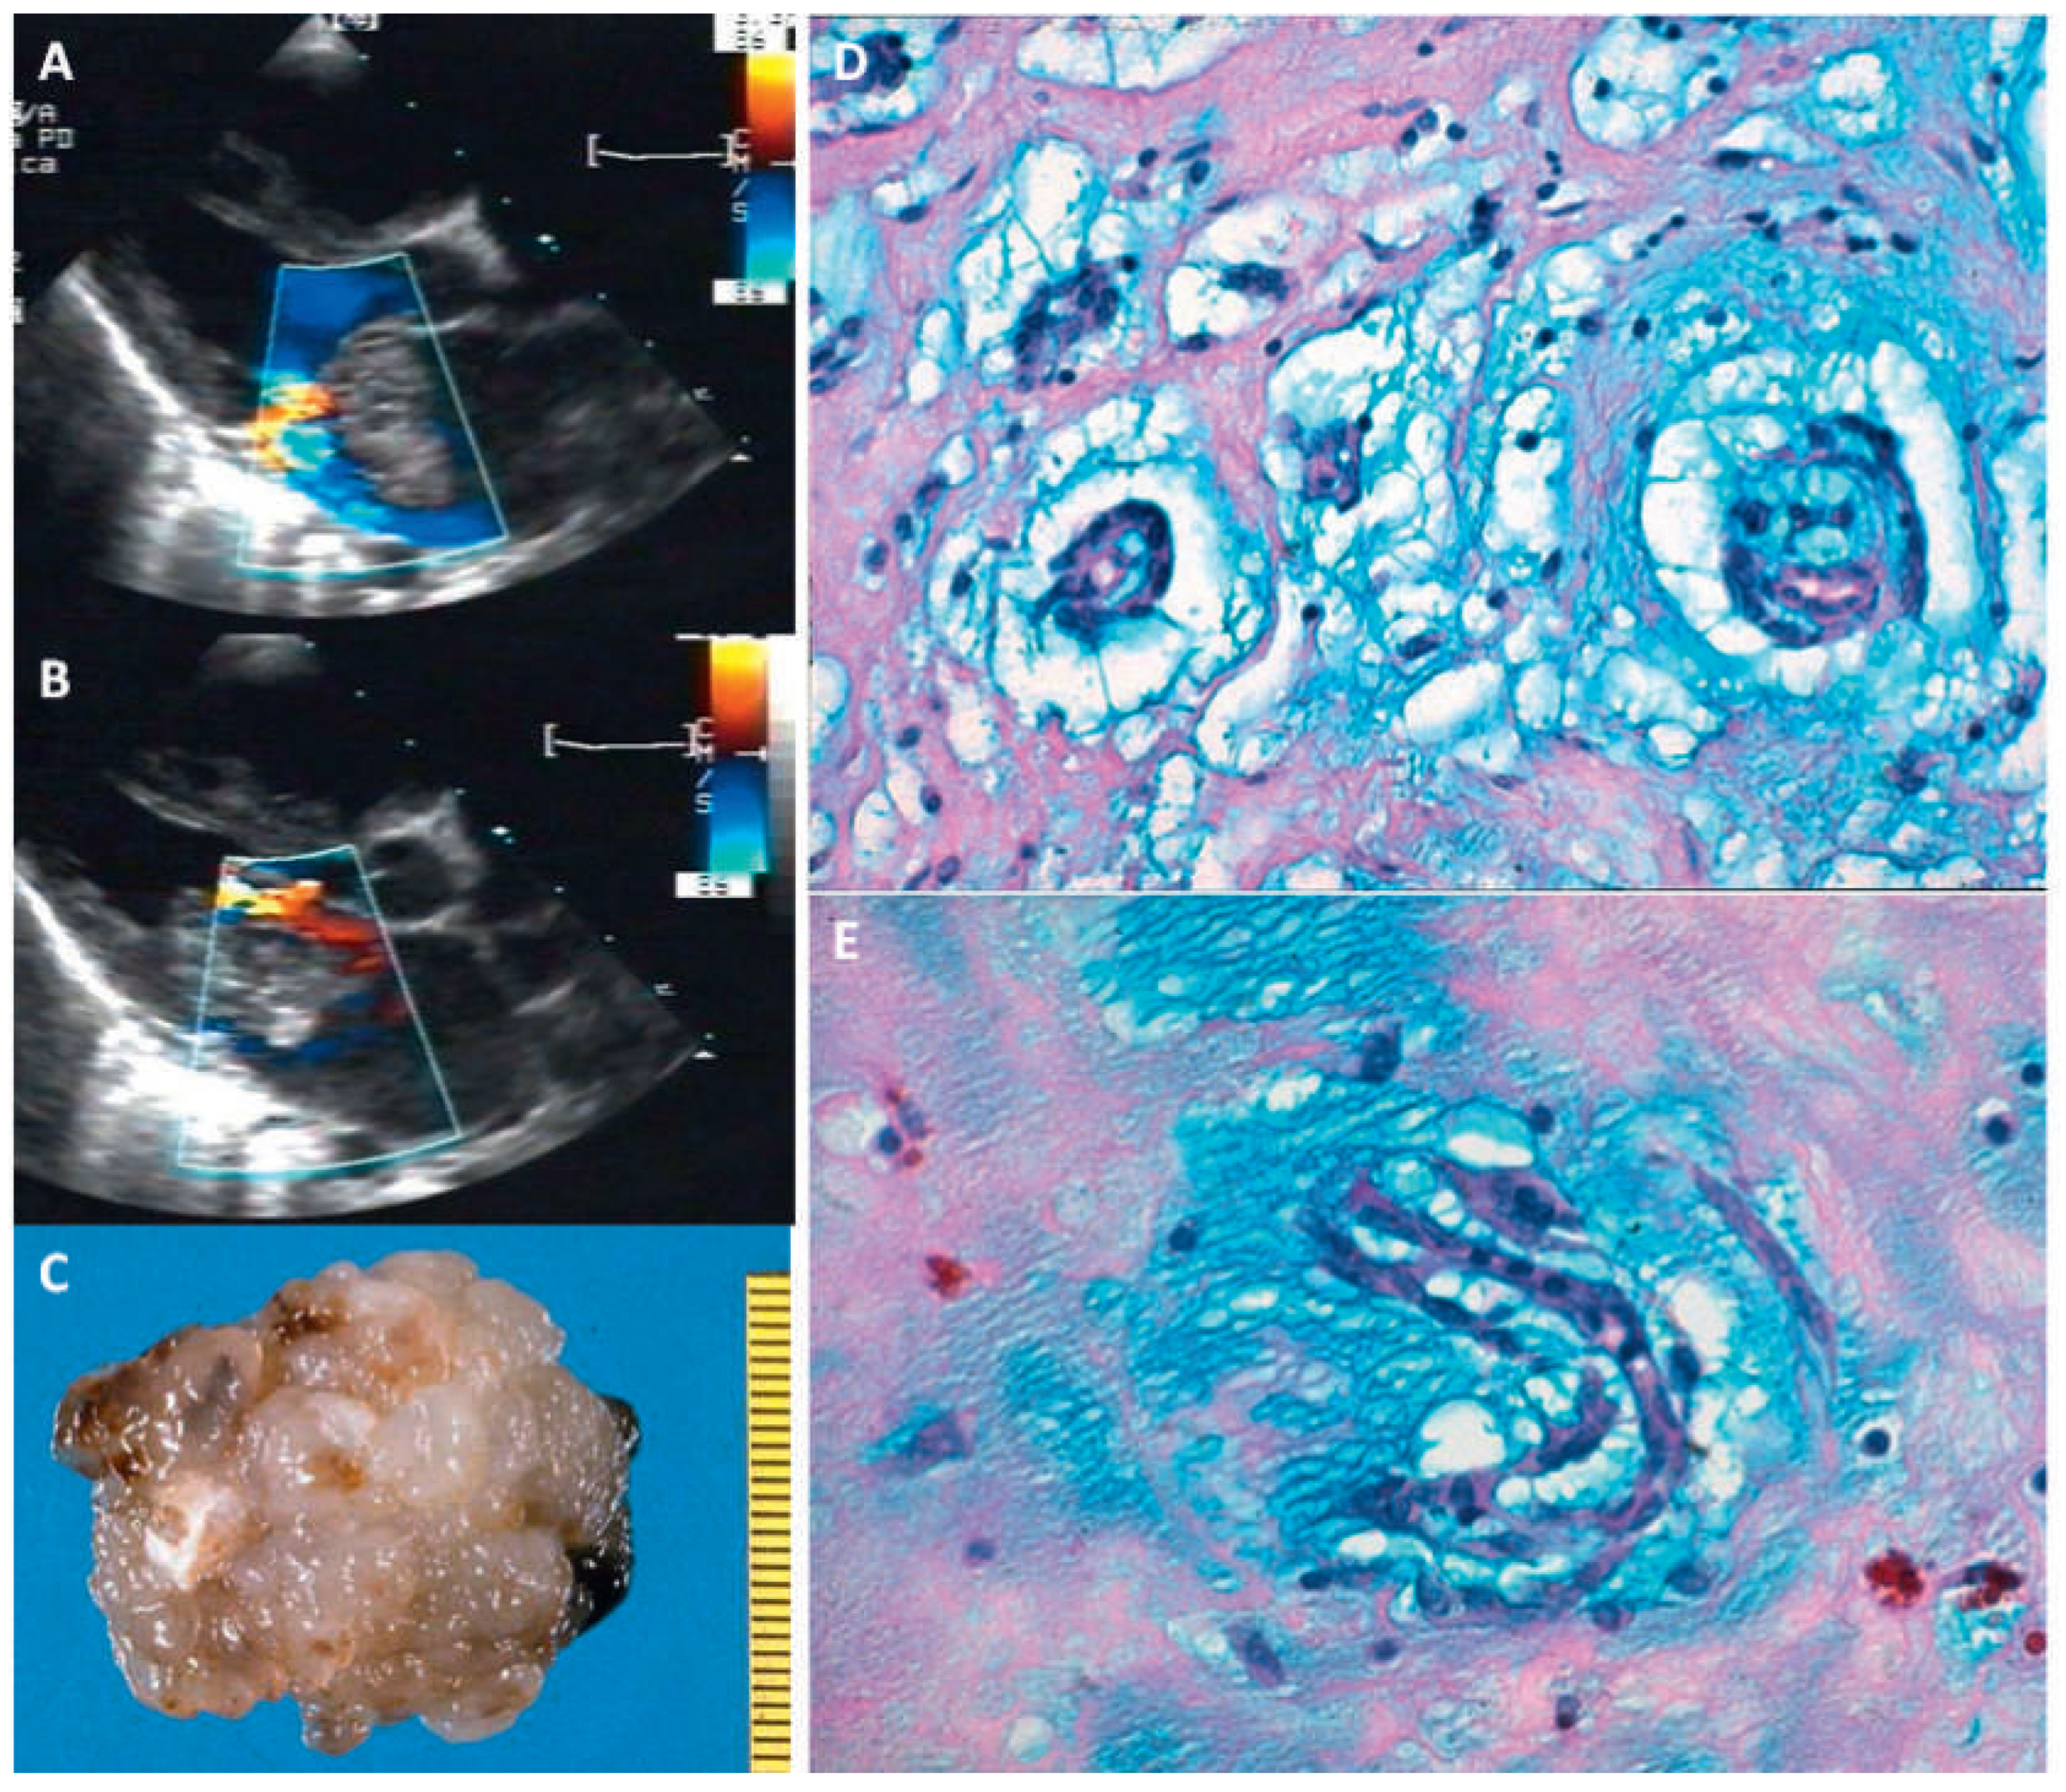

Angiosarcoma

- Poletti, A.; Cocco, P.; Valente, M.; Fasoli, G.; Chioin, R.; Thiene, G. In vivo diagnosis of cardiac angiosarcoma by endomyocardial biopsy. Cardiovasc Pathol. 1993, 2, 89–91. [Google Scholar] [CrossRef] [PubMed]